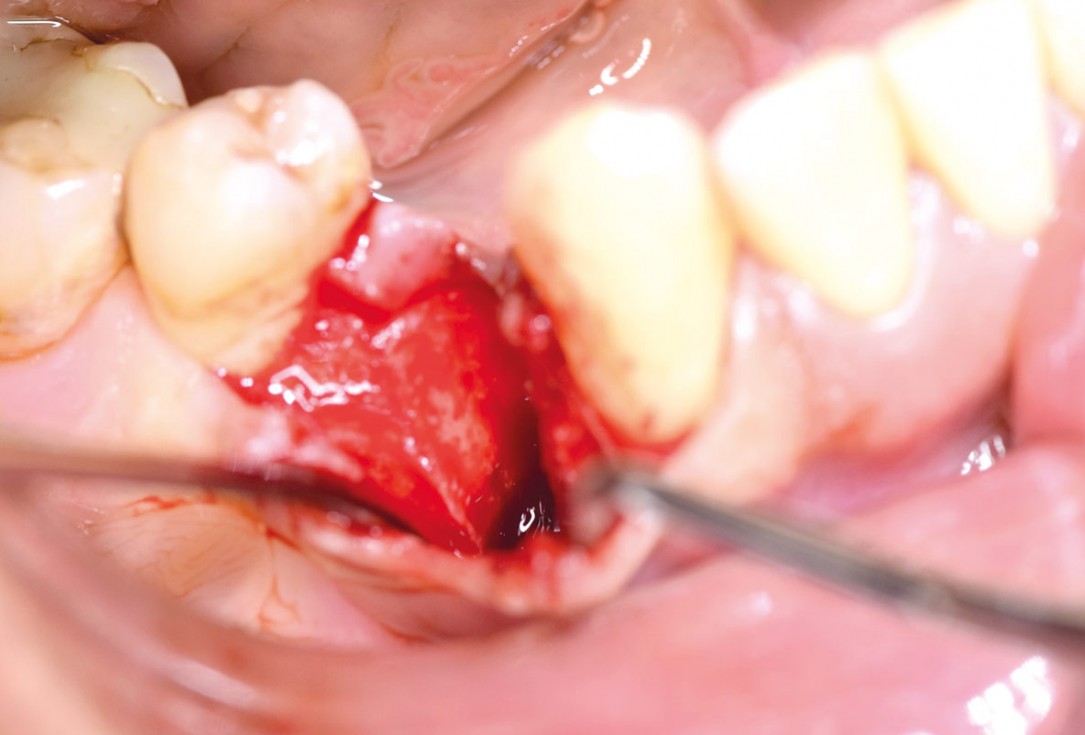

Preparation of a single tooth defect with severely resorbed vestibular wall

Posterior socket preservation using maxgraft® and permamem® - Dr. C. Landsberg